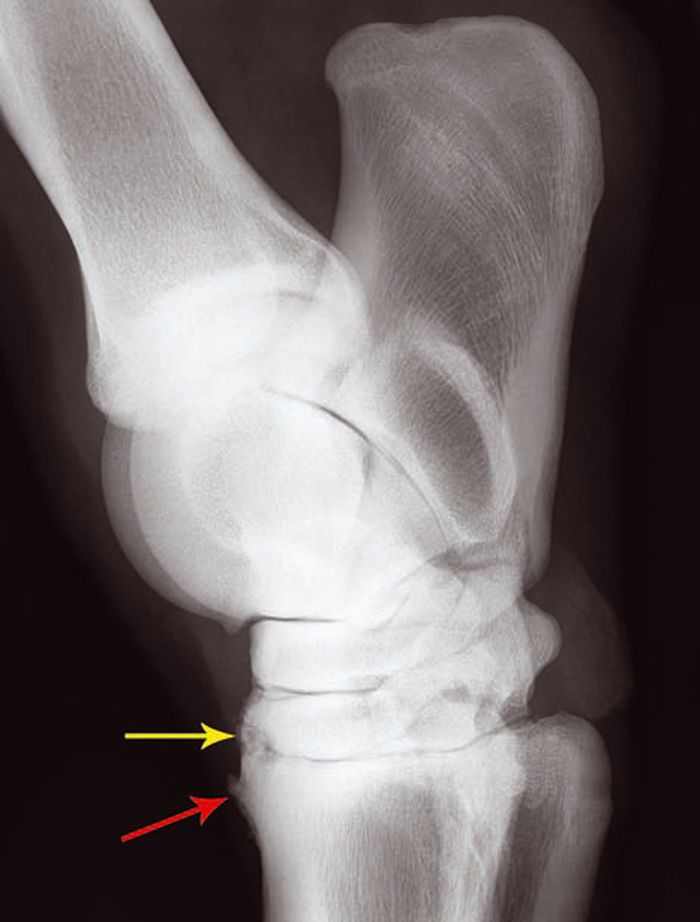

Bone Spavin in Horses: Symptoms, Treatment & Management

Currently, there are several different veterinary treatment options to control the pain and inflammation caused by OA, such as corticosteroid injections, platelet-rich plasma (PRP), stem-cell therapy and polyacrylamide gel injections.Polyacrylamide hydrogel decreased lameness in 82% of horses with naturally occurring osteoarthritis. Arthramid Vet’s 2. A significant difference is PAAG does not .Osteoarthritis (OA) is a degeneration of cartilage in the joint that gets progressively worse with age., 2014a; and McClure & Wang, 2017) which in turn could reduce pain (Silva Cabete, 2018). Journal of Orthopeadic Research and Therapy, 6 (2). 3 year results from a prospective study of polyacrylamide hydrogel for knee osteoarthritis . Previously IA PAAG has been investigated using 2 injections of 3 ml separated by a month.A prospective study of polyacrylamide hydrogel for the treatment of osteoarthritis in 43 horses reported a significant decrease in lameness, 82.

treatment of stifle injuries in horses can be difficult but a new treatment, Arthramid Vet 2. This was wrong. “The prevalence of OA is thought to be greater than 50% in horses older than 15 years,” Jarvis says, so there’s a good chance you’ll deal with it at .5% polyacrylamide hydrogel (PAAG) is effective, long-lasting, and safe for treating early- and late-stage equine osteoarthritis. January 12, 2024.An expert reviews material showing 2.5% PAAG, is offering veterinarians, owners and trainers a new option.In horses with naturally occurring osteoarthritis, is treatment with intra-articular polyacrylamide gel more likely to reduce the severity of clinical signs associated with lameness when compared to treatment with intra-articular corticosteroid? Clinical bottom line Category of research question. Methods This multi-centre, open-label study included patients with symptomatic and .5% free of lameness horses at two . Sport horses were hand walked days 1–5, walked under tack for days 6–10, then could trot under tack on days 11–20 if serviceably sound before returning to full work.Efficacy of a Polyacrylamide hydrogel in horses with symptomatic osteoarthritis: An International Multi-Centre prospective study.Polyacrylamide hydrogel (PAAG) was evaluated recently to treat osteoarthritis (OA) in horses with highly encouraging results; however no long term field-study was done to explore its clinical efficacy and lasting effect.Tnibar A, Schougaard H, Camitz L, Rasmussen J, Koene M, Jahn W and Markussen B. Here we report longer-term effectiveness and safety data. The decrease in lameness was present in 75% of the horses 90 days after . Twelve studies; four case series, .Equine osteoarthritis: is intra-articular polyacrylamide gel more effective than corticosteroid in improving lameness? Veterinary Evidence.

Effektivität von Polyacrylamid-Hydrogel bei Pferden mit Osteoarthritis.The effect on the synovial membrane and joint capsule and the long-acting viscosupplementation represent new concepts in the management of equine OA. This is in contrast to results seen with TA-HA treatment of 15% improvement at 1 month, 40% improvement at 3 months, and 35% improvement at 6 months.Purpose: Intra-articular (IA) injection of polyacrylamide hydrogel (PAAG) has been suggested as a possible treatment for symptomatic osteoarthritis (OA). The objective of this study was to evaluate the efficacy of PAAG in improving clinical signs of OA in horses. However, no researchers had previously investigated PAAG’s .Objective There are few effective osteoarthritis (OA) therapies.Long-lasting – non-absorbable.At enrollment, the client was given an exercise protocol relevant to the management of the horse. A novel injectable polyacrylamide hydrogel (iPAAG) previously demonstrated efficacy and safety up to week 26 in an open-label study of knee OA.Assessment of the safety intra-articular (IA) polyacrylamide gel (PAAG) treatment for knee OA symptoms found no significant incidence was noted of serious adverse events related to IA treatment with a proprietary 2. A variety of treatment options are available, but there is no single treatment that is .Another option— polyacrylamide hydrogel (PAAG) —is showing promise, according to a growing body of cross-species research. This histological appearance persisted up to 2 years post-injection in horse . An international multi-centre prospec- tive study in the efficacy of an intraarticular polyacrylamide hydrogel in horses with osteoarthritis: a 24 months .When treating horses with osteoarthritis, veterinarians can choose from many therapy options.1055/s-0038-1638243.Non-Pharmacological treatment offers veterinarians a better option for older and metabolic patients suffering from osteoarthritis (OA).Polyacrylamide gel may provide viscosupplementation and aid joint lubrication (Tnibar et al. The majority of vets recommend physiotherapy treatment for horses with osteoarthritis to help manage the symptoms and ensure the horse . Epub 2018 Mar 23.Don’t: Assume it’s Only Arthritis. Therefore, studies that investigated.Early Stage Equine OA: Vets Consider 2. Horse; osteoarthritis, medication, 2.What We Know About 2.Polyacrylamide hydrogel (PAHG) is being developed to treat osteoarthritis in horses.Osteoarthritis is one of the most common disease processes effecting equine athletes, causing up to 60% of all lameness.5% Polyacrylamide hydrogel (PAAG) is highly effective (82. Horses with OA may exhibit lameness, reduced range of motion in one or more joints, joint swelling, heat, and pain on manipulation of the affected joint. ArthramidVet is indicated for the management of non-infectious causes of joint disease in horses and dogs.5% iPAAG technology is injected . The primary objective of this study was to evaluate the efficacy and safety of a single injection of 6 ml intra-articular PAAG on . This prospective longitudinal study reports on the effect of treatment of .Bowkett-Pritchard, C. The number and type of study designs reviewed.Polyacrylamide hydrogel is used in the treatment of mild to moderate osteoarthritis in both humans and horses.com/1117837/what-is-polyacrylamide-gel/?lid=8s7dyb0r2s4t) The objectives of this study are to evaluate the clinical, cytologic, histologic, and metabolic effects of PAHG in normal fetlock joints. Others believed it was coating nerves and, therefore, masking pain. Prior to application in osteoarthritic joints, evaluation of PAHG in normal joints is indicated.5% Intra-Articular Polyacrylamide Hydrogel – The Horse.The carpus (knee) of the horse is comprised of three joints, with 2 rows of 7 (or sometimes 8) carpal bones between the radius (forearm) and the canon bone.5% of the 43 horses were sound at the 2- year .com/1117837/what-is-polyacrylamide-gel/ Posted by Stacey Oke, DVM, MSc.The long-term safety of the gel is not yet fully known, but a 2022 systematic review determined polyacrylamide hydrogels were deemed to be an efficacious and safe treatment option for knee OA and provides positive results for at least two years.